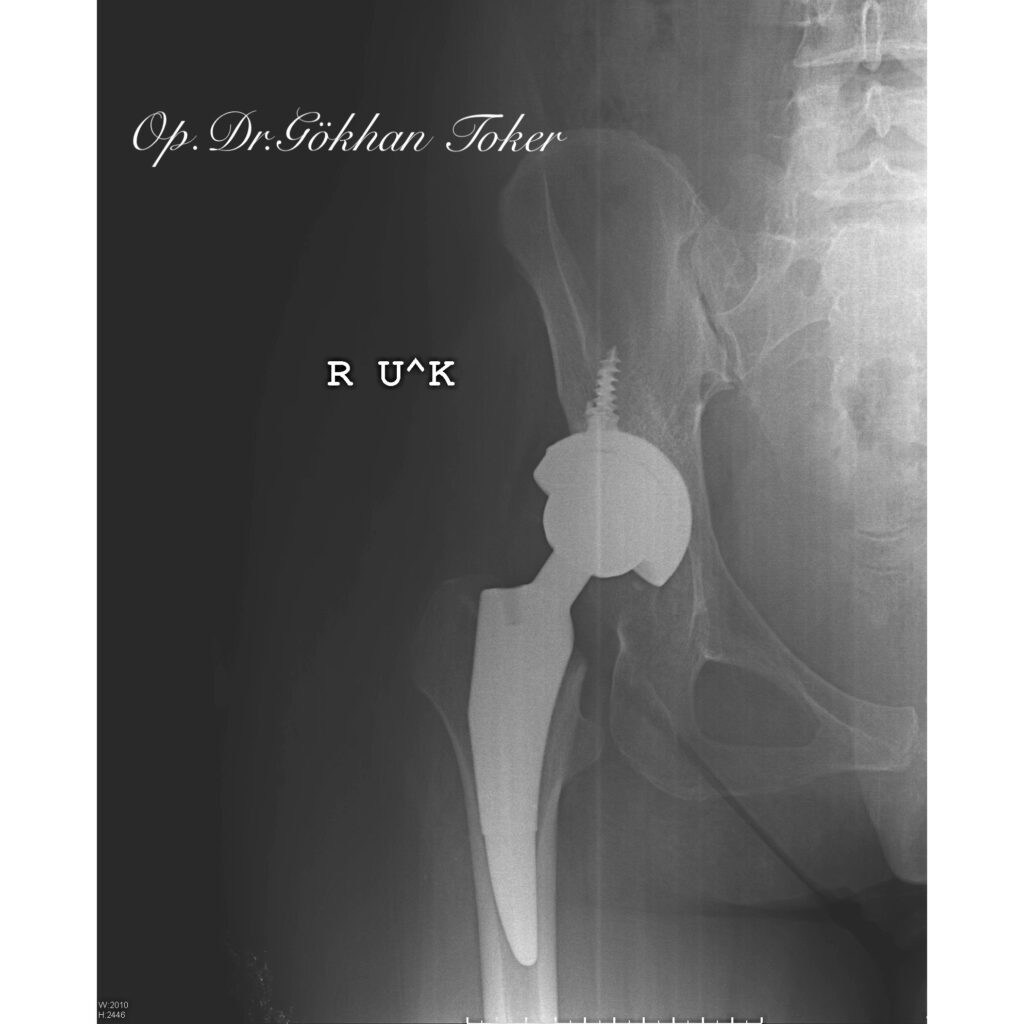

Ç.A.